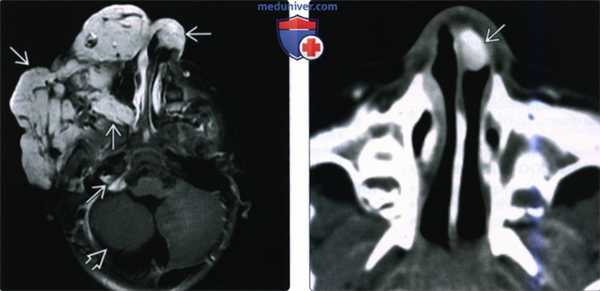

(Слева) При аксиальной МРТ Т1 ВИ С+ FS визуализируется контрастирующаяся гемангиома лица справа с поражением кожи и подкожной клетчатки. Определяется потоковое выпадение сигнала во внутреннем слуховом канале (ВСК) справа (норма). Слева потоковое выпадение сигнала отсутствует в результате атрезии ВСК.

(Справа) При аксиальной MPT Т2 ВИ у этого же пациента определяется гипоплазия мозжечка и мальформация его коры с расширением замозжечкового ликворного пространства. Мост с вентральной стороны уплощен и уменьшен в размерах.